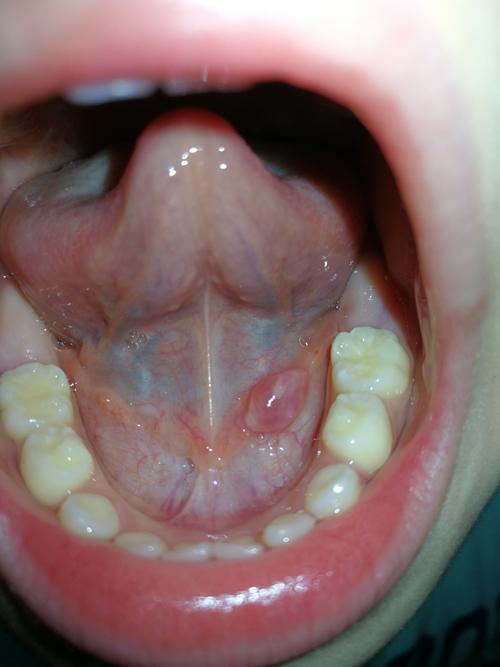

正常人舌头下面 肉芽,舌头下有小肉芽正常吗

舌头下有小肉芽正常吗

正常舌头底下肉芽图片

舌头翘起来底下有肉芽

正常舌头卷起下面图片

正常人的舌头底部图片